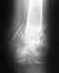

Неправильно срослась ключица (последнее времия становится все болееочевидно - не только на ощупь но и визуально).Ранее не так сильно было заметно. Прошу совета (а лучше помощи,территориально нахожусь в Москве).

К сожалению не могу точно определить момент перелома.Активный образ жизни, экстремальные развлечения,повышенный болевой порог - в общем среди частых мелких травмпрозевал момент перелома. Ключица лопнула в сантиметрах 3-4 от плечевого сустава(похоже в месте изгиба). Видимо, когда он случился, принял за ушиб или легкий вывих.Перетерпел из забыл. Возможно прошло год - два. Поскольку не специалист - объянсить точно не могу из за чего,но за последние пару месяцев ситуация резго усложнилась:- плечо постоянно ноет,- при движении руки плечо "щелкает" (пару раз клинило), иногда незначительная больили онемение возникают в мизинце и безимянном пальце,- над плечем становится заметна небольшая шишка,- на ощупь заметна ступенька между костями примерно в палец высотой.Складывается впечатление, что кость начинает одновременно уходить вглубь в направлении лопатки и вниз.Как писал выше - нужен совет, а лучше помошь(если возможно).